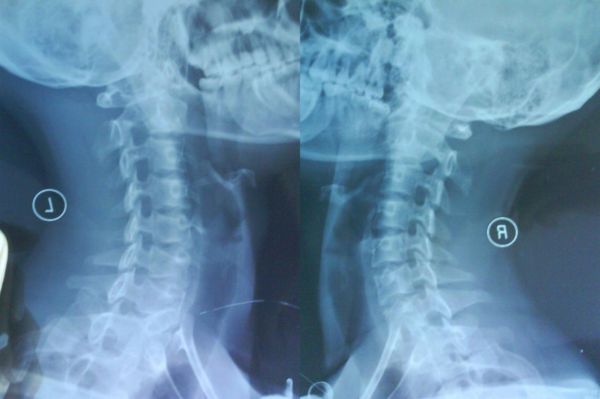

文章开始前,和大家分享一个最近遇到的颈椎病案例:24岁的小方是一名IT公司的职员,IT公司大家都知道,高强度工作,经常加班都是在所难免的,小方入职2年来,发生心慌、胸闷有半年了。在社区医院心血管科做全面检查简单调理后不见任何好转,更严重的是,长期的工作压力和种种不适症状引起他情绪低落,医生又诊断为抑郁症。最后到医院来检查颈椎时才发现,小方目前已经是颈2椎体偏歪。

颈椎有问题,在当下并非个例。据统计,我国颈椎病的发病率已经接近20%,在大多数人眼里,颈椎病好像是只有上了年纪的人才会患上的疾病,实际上,30岁以下的颈椎病患者已经占了接近四成,我们日常生活、工作中的不良姿势和习惯已经颈椎的负担越来越重,看似毫不相关的症状,其实都和颈椎问题有关。